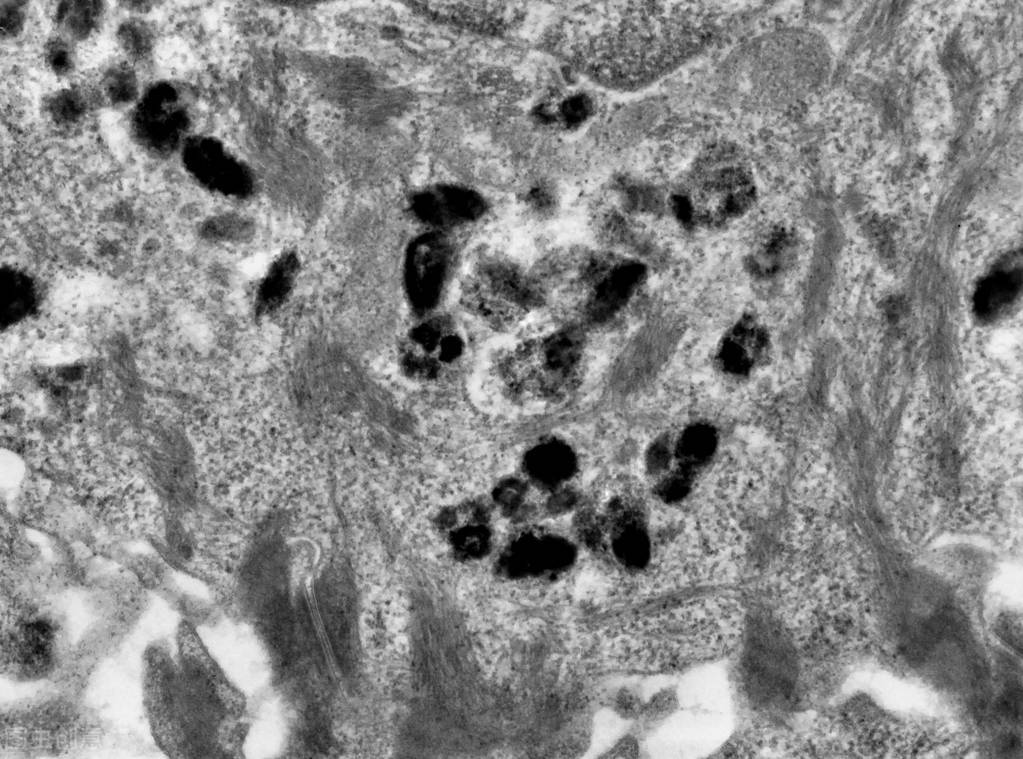

黑色素细胞相当于“工厂总部”,黑素小体(黑色素细胞的细胞器)相当于“生产车间”,酪氨酸是“基本原料”,酪氨酸酶基因家族蛋白中的酪氨酸酶(TYP)、酪氨酸酶相关蛋白等则是“合成工具”,合成的“产品”是真黑素、伪黑素。真黑素的含量越丰富,肤色越暗沉;伪黑素的含量越丰富,肤色越亮白。黑素被转运至角质形成细胞中,构成皮肤的色素屏障,影响我们的肤色。